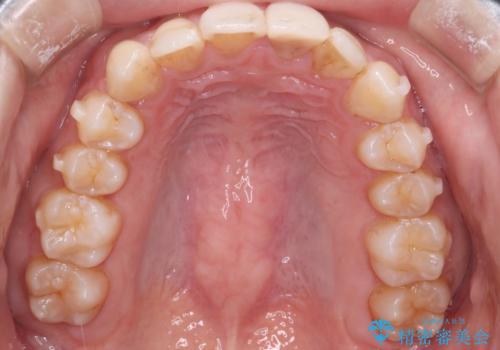

- 前歯のがたつきと口元を下げたいとのことで来院されました。

骨格的に左右差があるので正中を合わせることと抜歯矯正での口元改善は難しいことを説明させていただきました。

患者様に理解していただいた上で、インビザラインにてIPR(歯と歯の間を削る処置)を行いながら前歯のがたつきを整える治療計画を立てました。